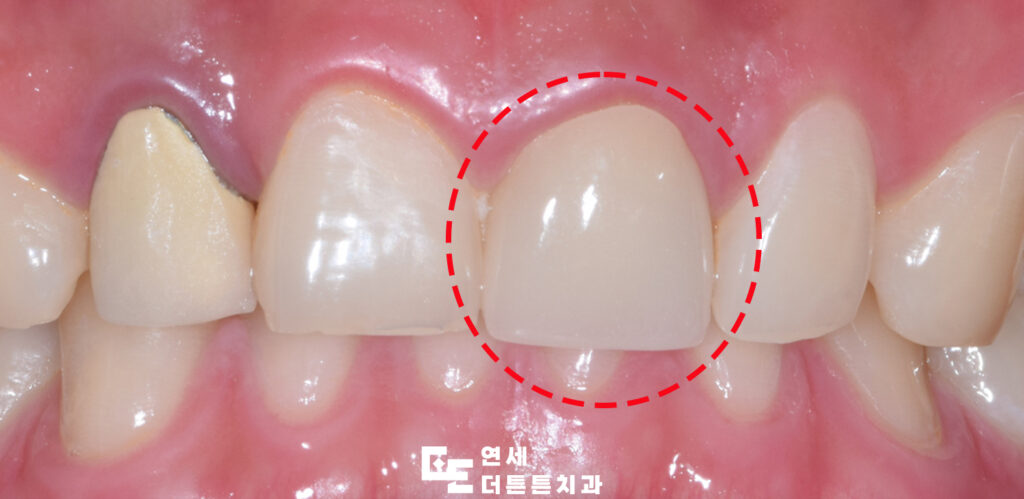

환자분께서는 앞니가 까맣게 보이신다며 충치치료를 위해 방학역치과에 내원해 주셨는데요.

크라운 수복을 마무리한 모습입니다.